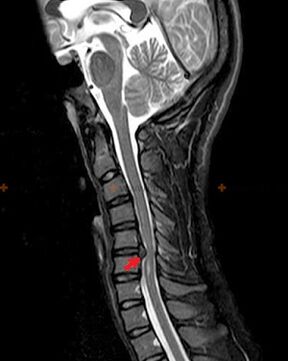

Do diagnozowania osteochondrozy stosuje się następujące metody badawcze: radiografię (najlepiej z testami funkcjonalnymi), MSCT i MRI. To drugie badanie jest najkorzystniejsze ze względu na to, że pozwala bardzo wyraźnie zobrazować stan struktur międzykręgowych.

Obecność opisanych powyżej zmian, a także zmiany w budowie krążka międzykręgowego wykryte w badaniu MSCT i MRI, są wiarygodnym sygnałem potwierdzającym obecność osteochondrozy.